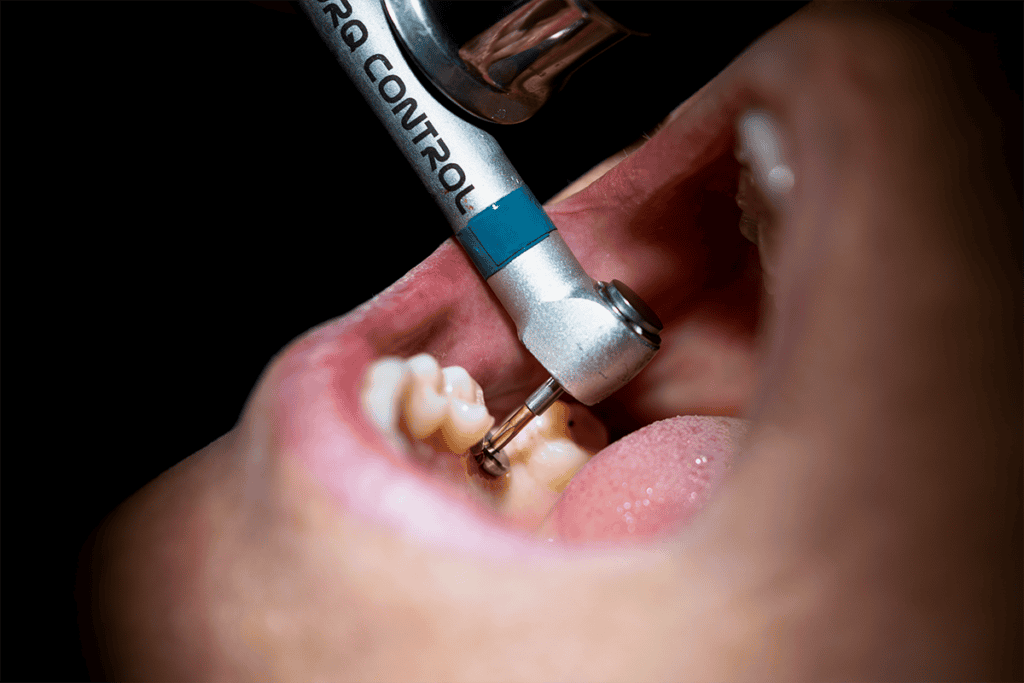

For those missing one or a few teeth, dental implants offer a versatile and highly effective solution. A dental implant is a titanium post surgically placed into the jawbone, serving as a strong foundation for a crown, bridge, or denture.

- Deep cleaning (scaling and root planing): To remove plaque and tartar from below the gumline.